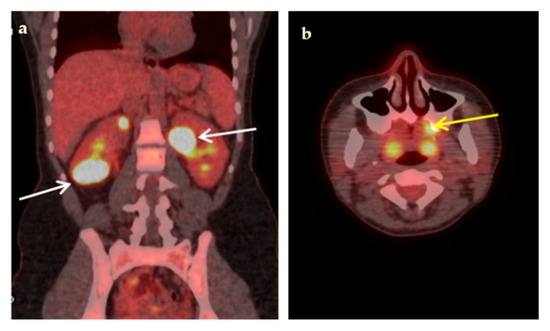

| Infections | 19 | 0 | 0 | 1 | 20 |

| Malignancies | 8 | 0 | 0 | 0 | 8 |

| Non-infectious inflammatory diseases | 9 | 2 | 0 | 0 | 11 |

| Undiagnosed fever | 0 | 4 | 6 | 1 | 11 |

| Total (%) | 36 (72%) | 6 (12%) | 6 (12%) | 2 (4%) | 50 |